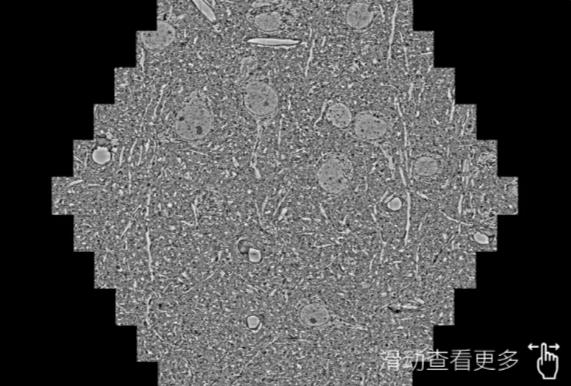

鼠脑切片。左图使用武隆蔡司武隆扫描电镜MultiSEM706对165μmx143pm面积区域成像,耗时仅需1.5秒。右图为鼠脑切片中30μm区域放大效果。样品由芝加哥大学B.Kasthuri提供。

使用蔡司高速武隆扫描电镜MultiSEM对1mm²人脑皮层组织进行高分辨成像,并对其中的各种细胞结构进行三维重构分析。左图展示了2x3mm²组织平面中锥体神经元的三维重构效果。右图显示了局部体积神经元三维重构。图像由哈佛大学chtman实验室提供,渲染图由D. Berger 制作。